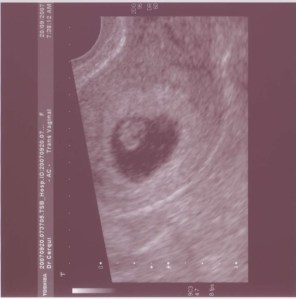

You often talk about how lucky you are, but I wanted to tell you how lucky your Dad and I feel, every single day, to have you. It took us a long time and much heartache to get you, but when we first saw you as a tiny cluster of cells, and heard your heart beating, our lives changed forever.

I loved being pregnant with you, although it was also scary because I worried a lot that something might go wrong. Things had gone very wrong for me before, so the fear was real. But they say that some women blossom during pregnancy, and my obstetrician definitely thought that about me. At my 30 week check-up appointment, he walked into the room, stopped in his tracks and said ‘Look at you!! You look absolutely amazing, you are just glowing’. He was so excited about how well I looked that he proceeded to call in the nurse to come in marvel at my heavily pregnant self. Having you inside me might have made me need to go to the toilet approximately every 35 seconds, but it also made me shine from the inside out.